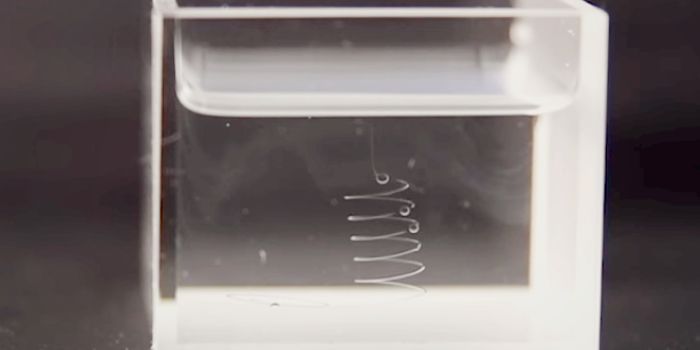

NOV 02, 2016Chemistry & PhysicsDiagnosing Sepsis Earlier to Save Lives Using Microfluidics